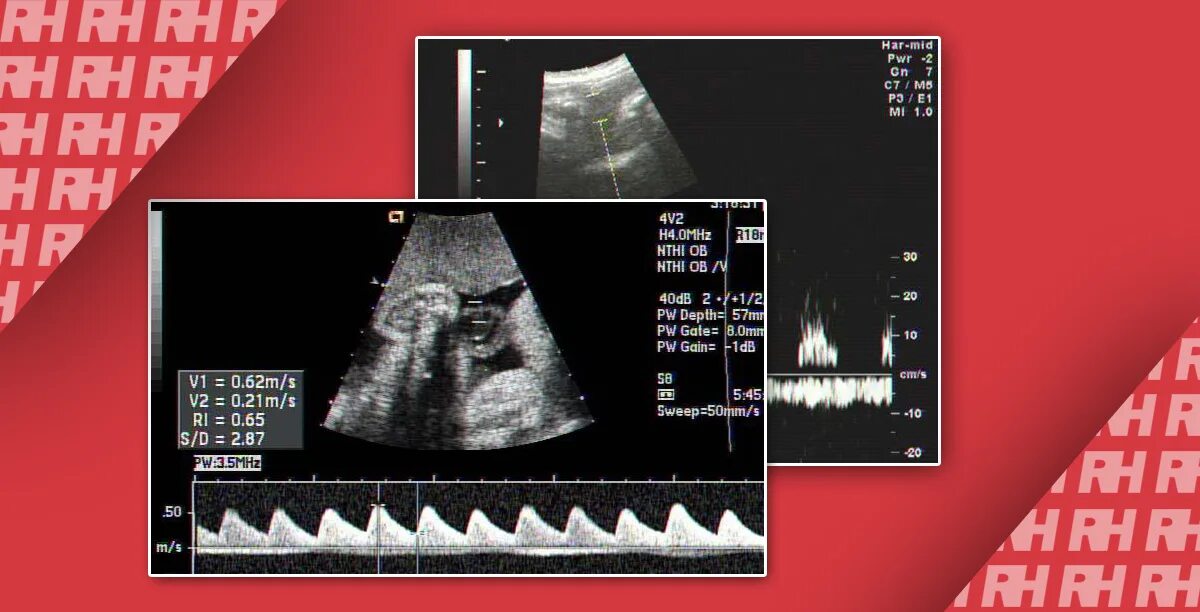

Надпочечник не визуализируется что это значит